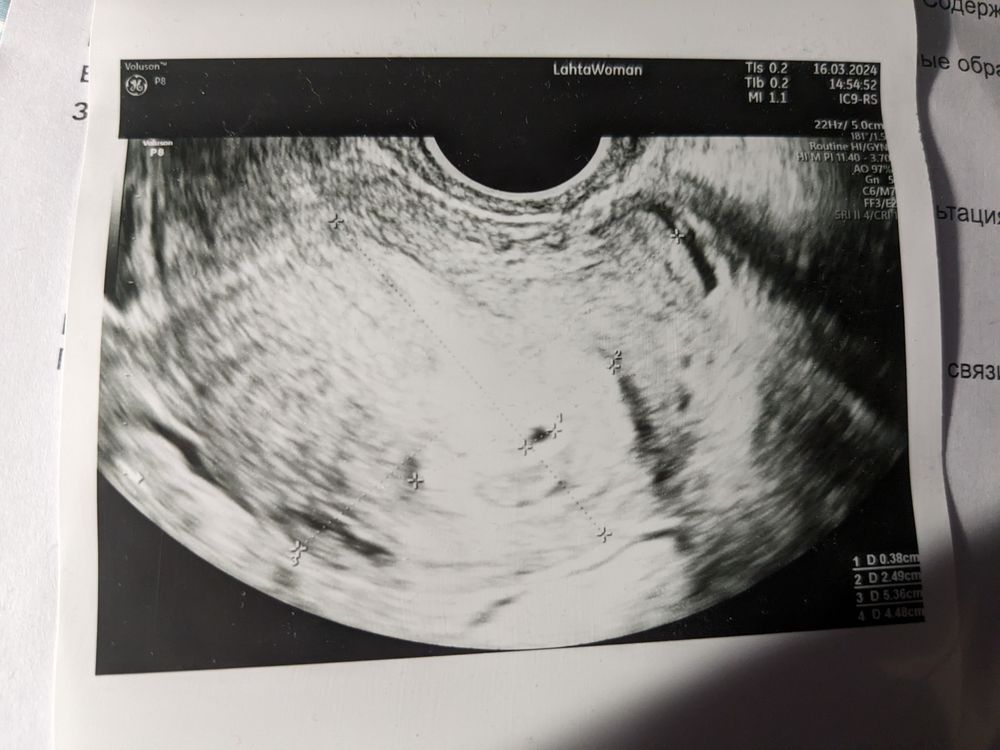

Алёна, нет, видео у меня нет. Роды естественные, никаких гинекологических диагнозов. Про цдк пришлось погуглить - делали обычное, но когда смотрели эту точку в матке, доктор включала что-то цветное. Вот протокол: Изображение

Ксения, на таком ХГЧ и в трубе плодное яйцо не видно, у вас на фото обвели что-то с неровными краями, у пя обычно края четкие. Не исключайте, на всякий случай, внематочную.

Виктория, я не знаю, почему именно такой снимок сделали, но в процессе эта черная точка была очень даже ровная. Но да, при таком раскладе исключать вообще ничего нельзя...

Ксения, цветное - смотрела, есть ли кровоток. Протокол ничего не говорит, по фото тоже непонятно. Понятно только, что это жидкостное включение, но для ПЯ очень рано, хотя похоже конечно. Возможно, ниша, киста, миома, да что угодно на самом деле. Надо смотреть в динамике.

Ксения, вероятно, та точка на УЗИ - ниша с кровью, изначально шло отторжение. В любом случае, главное, что всё хорошо. Просто не в этот раз. Значит, в следующий. Наш организм - большая генетическая машина, значит, так было нужно и правильно.